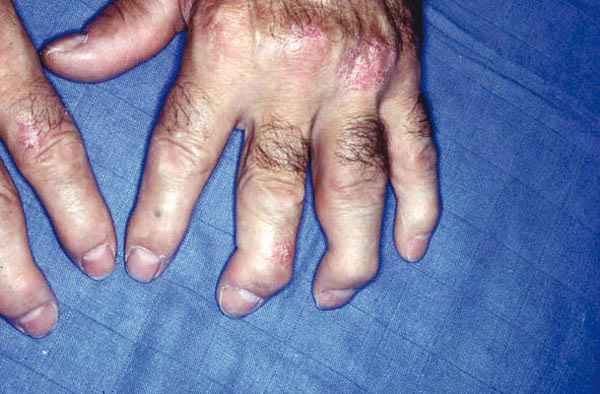

Le tableau clinique typique est constitué, chez une personne atteinte de psoriasis, par la survenue de douleurs articulaires d’horaire inflammatoire, révélant des arthrites périphériques, de forme oligoarticulaires et asymétriques le plus souvent, et pouvant atteindre les articulations interphalangiennes distales (fig. 1 et 2). Les manifestations cutanées du RP comprennent le psoriasis (généralement psoriasis en plaques) et le psoriasis unguéal, souvent marqué par un épaississement de l’ongle ressemblant à une mycose.

La présentation est variable et on y trouve des éléments du spectre des spondyloarthrites, puisque le rhumatisme psoriasique fait partie de ce groupe de maladies. On observe chez environ un tiers des patients atteints de RP, au cours de leur vie, l’apparition de dactylite (inflammation de l’ensemble d’un doigt ou d’un orteil) et /ou d’enthésite (inflammation des insertions des tendons dans l’os).